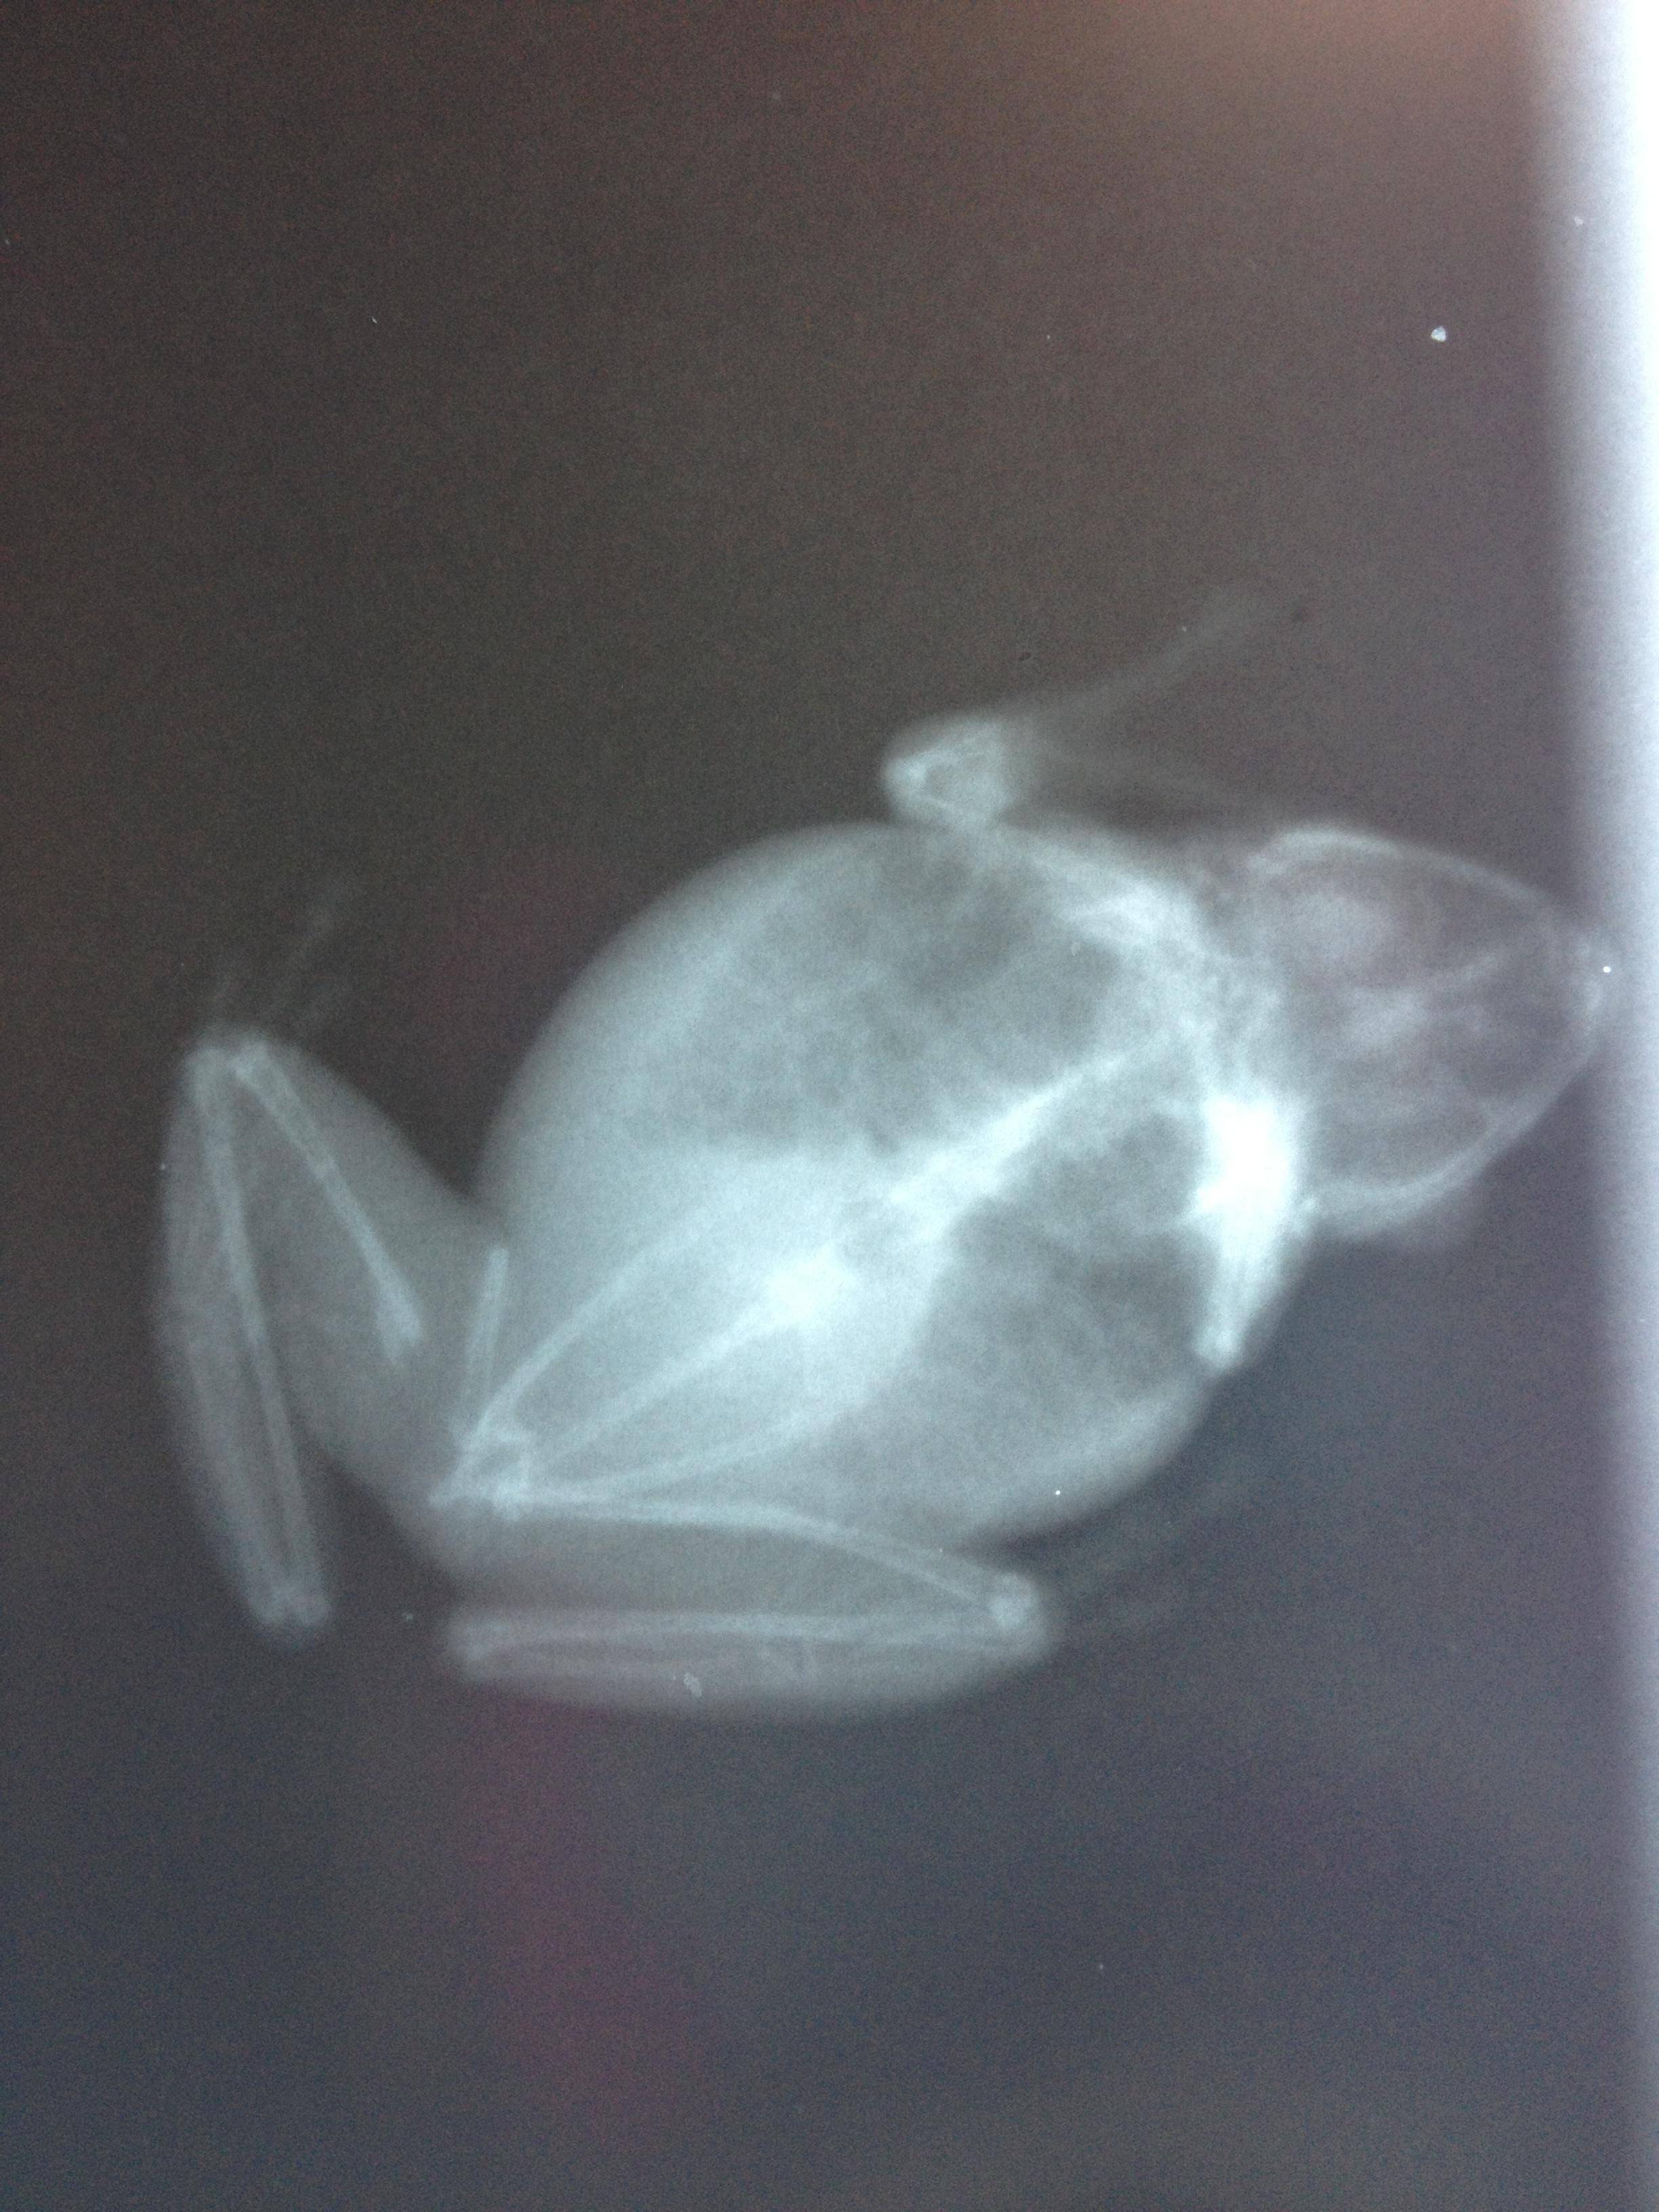

Alright, so the vet squeezed me in once I told them I thought her leg was broken. Didn't even have to wait very long too. Her weight is 13g, down from 16 when I took her 2 months ago. He did inform me that he did use Panacur last time for the worms, and he did give her some more. He thinks that since she had nothing but pinworms last time that maybe some were in her muscles and seaped out after the others were gone. She does infact have a broken leg

Attachment 53470Attachment 53471

He told me if her bones were large enough he could stick a pin in and set it, but since she is so tiny, she will just have to heal on her own. He did say her bones look great so I guess that's a plus (besides the broken one). I did pick up some water treatment stuff

I guess they didn't load but here are some pics I thought everyone would like to see!